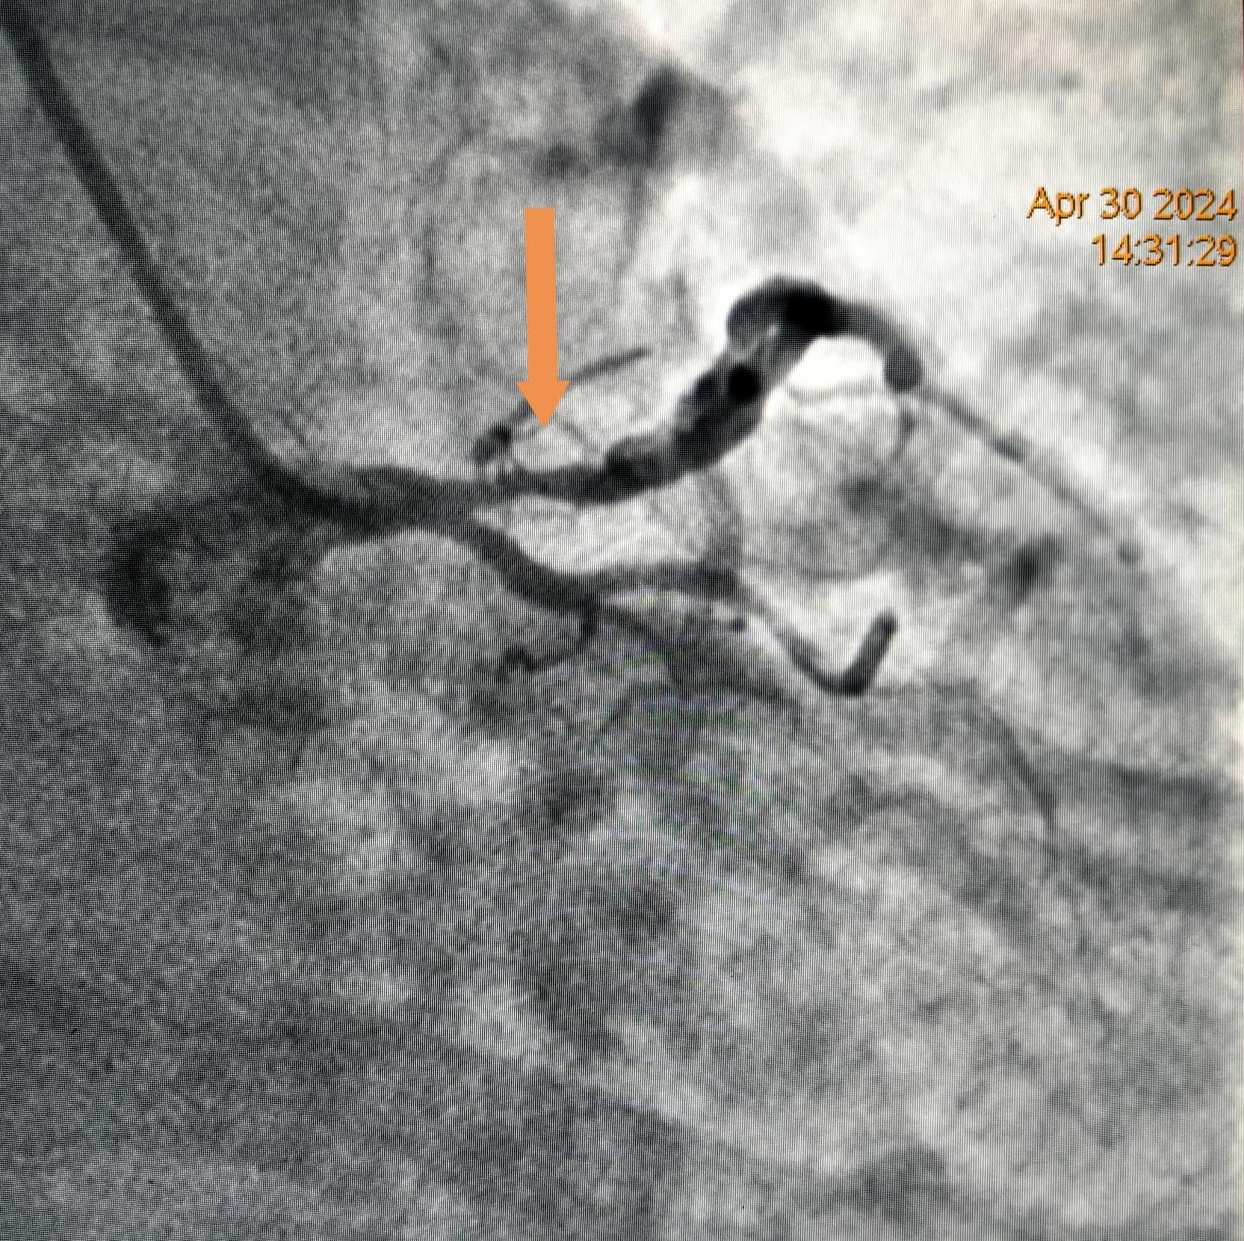

患者李先生,因“發作性胸痛伴咽喉部緊縮感2月”在我院心病一病區住院治療,冠脈造影檢查提示前降支近端狹窄85%。

治療前造影提示前降支近端85%狹窄